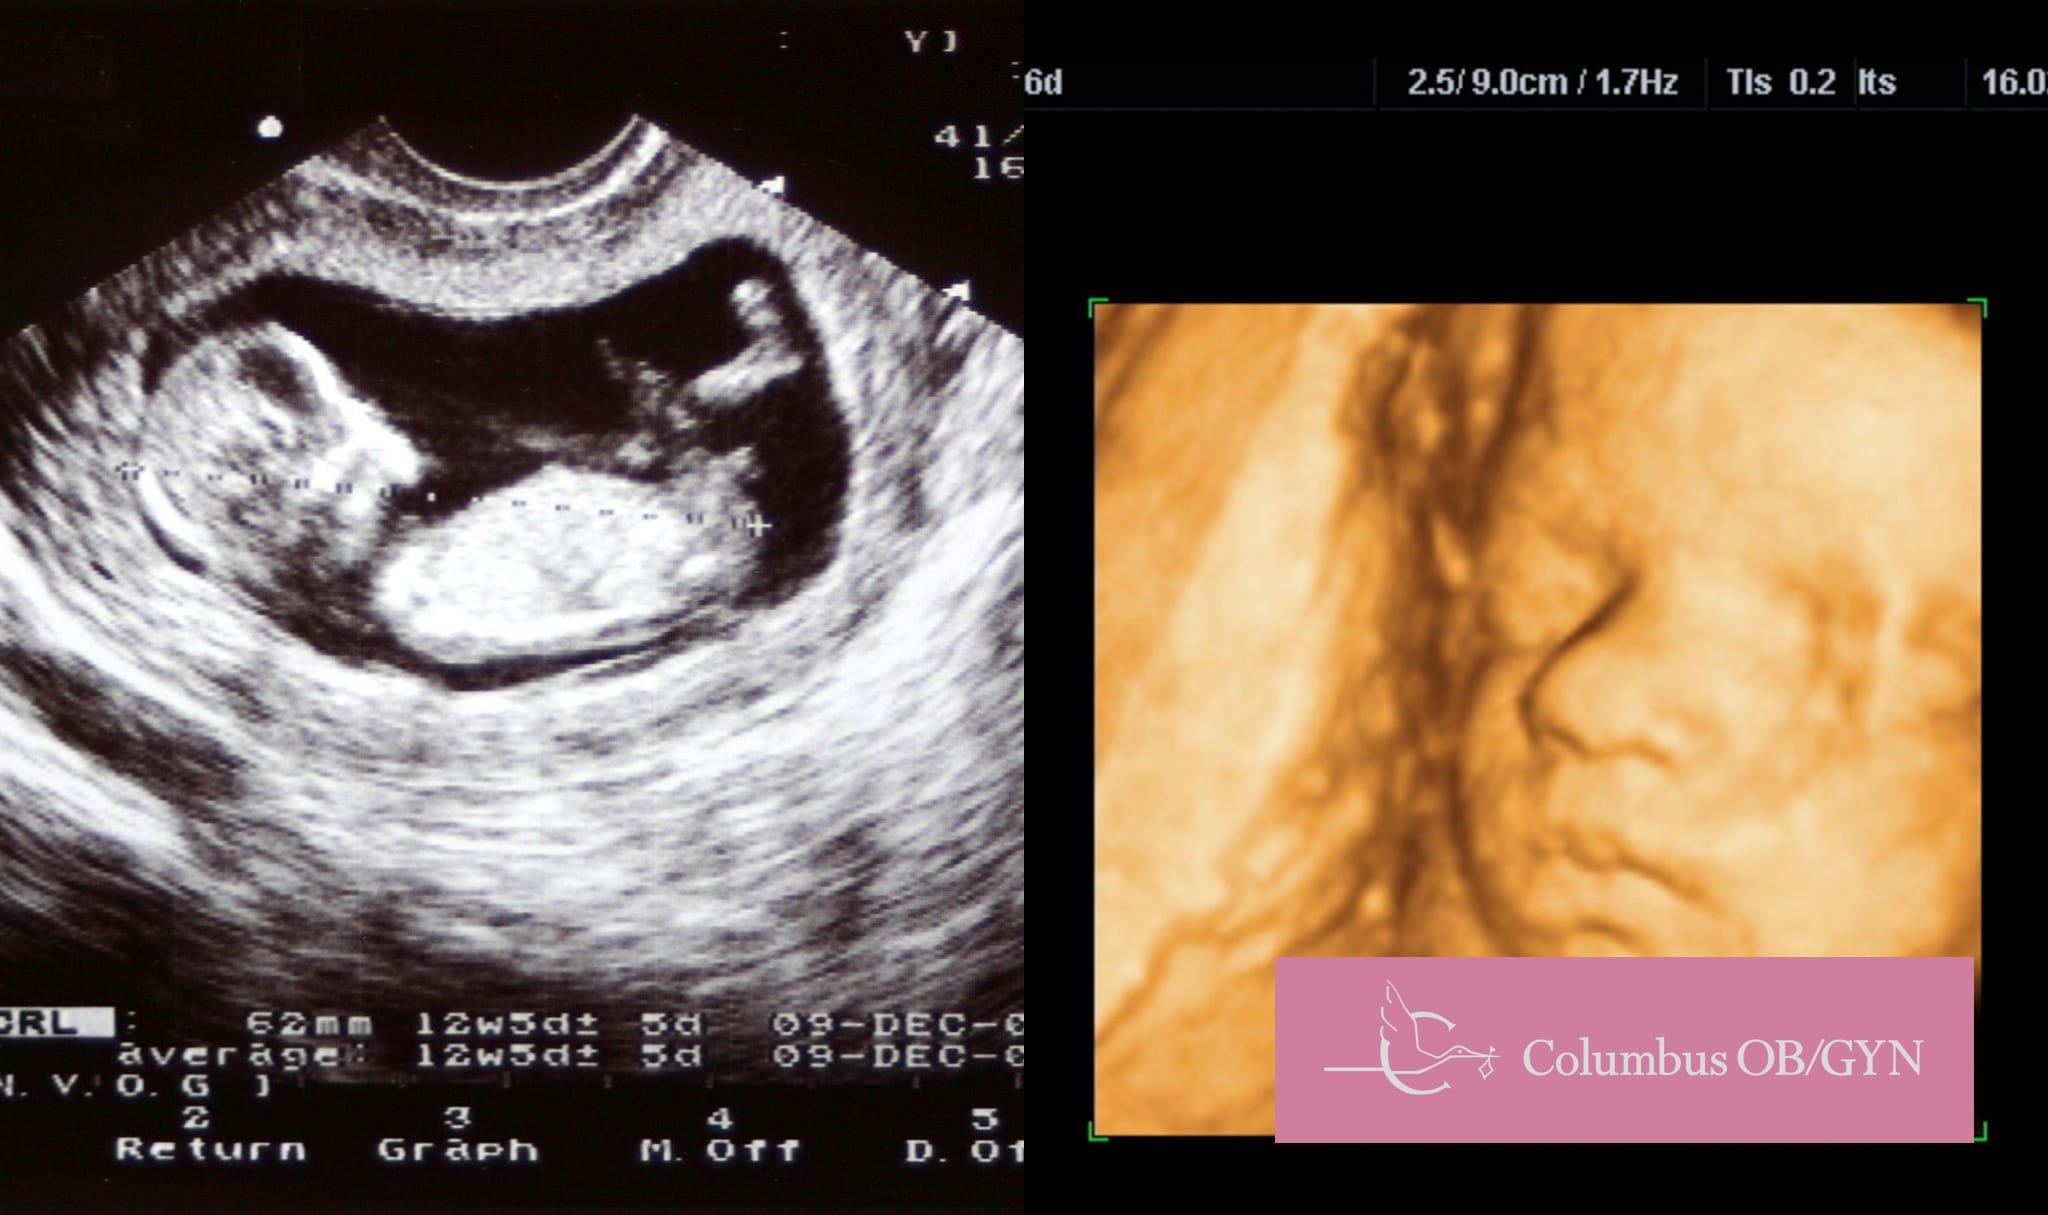

Traditional ultrasounds have served us well, but 3D imaging takes it further. With this advanced technology, every curve, contour, and feature of your baby is rendered with astonishing clarity.

Gone are the days of flat, two-dimensional images. 3D ultrasounds provide a depth of field, allowing parents and healthcare providers to view anatomical structures in an almost tangible way.

2D and 3D Ultrasound Services

3D ultrasounds offer a unique and detailed view of the baby, allowing parents to see facial features, expressions, and movements in a way that traditional 2D ultrasounds can’t capture. For many parents, this provides a deeper emotional connection and a memorable experience.

From a medical perspective, while 3D ultrasounds can offer improved visualization in some instances, they are typically considered a complement to, rather than a replacement for, standard 2D ultrasounds